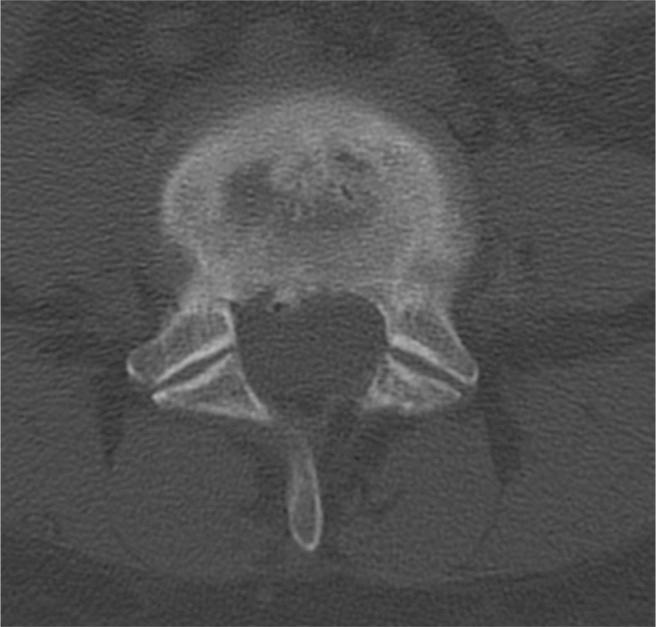

The patient was referred for genetic evaluation, which classified her with type III EDS, or hypermobility type. We presented the patient with the risks and benefits of fusion versus artificial disc replacement (ADR), particularly with regard to her EDS diagnosis of the hypermobility subtype. Given the patient's lack of extreme spinal hypermobility on examination and the absence of clear contraindications regarding ADR in type III EDS, the decision was made to proceed with ADR. There were no surgical complications, and the patient's low-back pain and radicular symptoms resolved with no evidence of implant migration or hypermobility at 1 year postoperatively.

该患者被转诊进行基因评估,结果将她归类为III型EDS,即活动过度型。我们向患者介绍了融合手术与人工椎间盘置换(ADR)的风险和益处,特别是考虑到她的EDS活动过度亚型诊断。鉴于患者检查时未出现脊柱极度活动过度,且III型EDS中ADR没有明确的禁忌证,因此决定进行ADR。手术无并发症,患者的下背痛和神经根症状得到缓解,术后1年无植入物移位或活动过度的迹象。